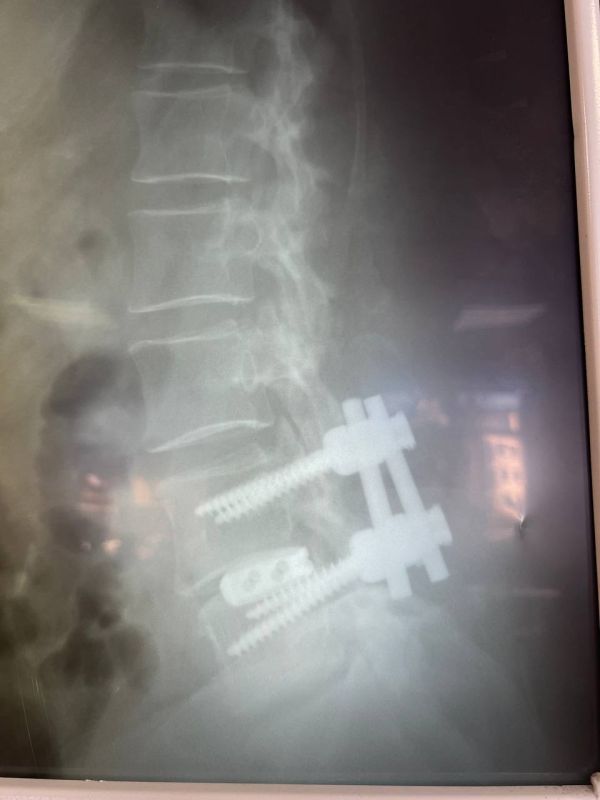

У пациентки выявили множество патологий, в том числе поражение межпозвоночных дисков, сужение пространства позвоночного канала.

В больнице № 11 врачи «разжали» позвонки с двух сторон, удалили грыжу и диски поражённых частей заменили на импланты.